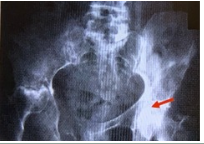

A 68 yo man presents to his physician's office with diffuse pelvic pain. XR of the abdomen for this patient is shown right. Which of the following would help to diagnose the primary tumor most commonly responsible for these radiologic findings?

a. Digital rectal examination

b. Palpation of the abdomen

c. Palpation of costovertebral angle

d. Palpation of the neck

e. Skin examination